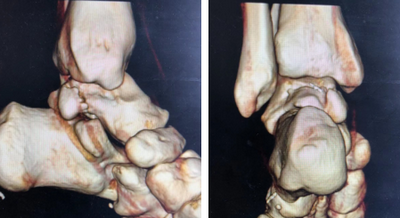

重建

入院第二天,石荣剑副院长、曹广超主任、周吉医生手术团队为患者进行了“左踝关节镜下探查清理+机器人辅助下距骨骨折复位内固定术”。术中于左踝后方内外侧两旁各取1cm纵行切口,钝性分离组织,向关节腔内放入关节镜镜头,探针探查见增生、水肿、炎性增生的滑膜,距骨内上缘软骨损伤,内侧三角韧带部分撕裂,刨刀去除增生、水肿的滑膜,去除损伤软骨。探查见距骨内侧及后侧骨折,局部粉碎,断端移位,用机器人辅助定位确定固定距骨2处骨折端螺钉方向,钉入2枚克氏针导针,并沿导针钉入2枚全螺纹空心螺钉,修复内侧三角韧带,C型臂透视见距骨骨折端对位对线良好,内固定在位。手术顺利,术后患者安返病房。